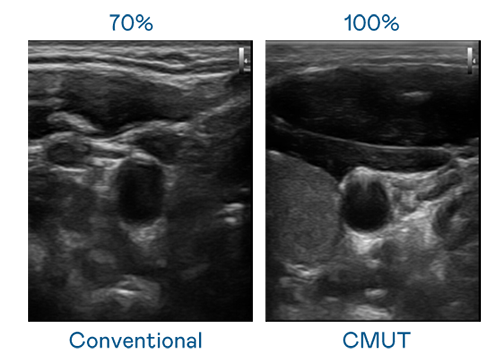

CMUT 技術是一種用電容式微機電元件來產生超音波訊號的技術。與傳統 PZT 壓電式技術相比,CMUT 頻寬增加 30%,更寬頻的超音波訊號讓影像解析度大幅提升,是實現高影像品質醫療超音波掃描、促進精準醫療發展的關鍵技術。

大頻寬帶來超清晰影像

超音波影像的解析度高低,首先取決於探頭能發出的訊號頻寬。5001拉斯维加斯 CMUT 可提供高清晰的超音波訊號,提供高頻寬、高靈敏度、影像紋理細節更高的超音波影像,協助醫護人員縮短影像判讀時間及利用精準的醫療影像進行診斷。